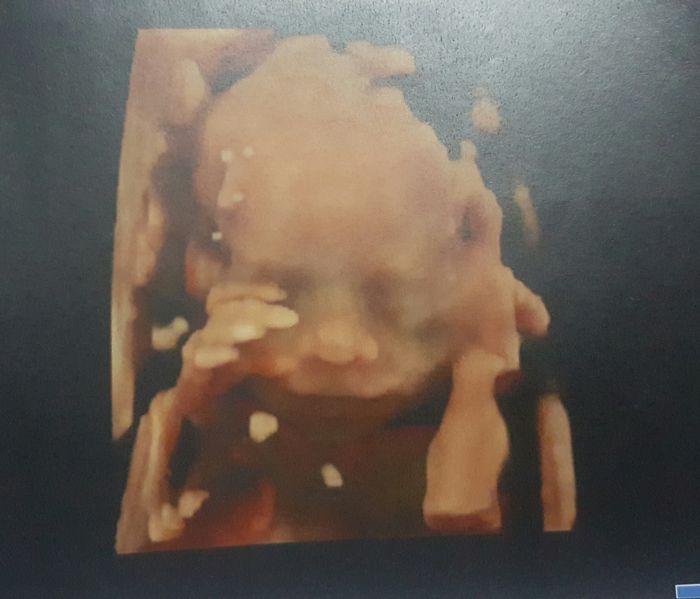

Ja byla v utery na velkem utz, a vse je tak jak ma byt, tak se mi hodne ulevilo. Doktor prozkoumal mrnouse od hlavy az k pate, vsechno mi vysvetloval a ukazoval, no muzu rict ze ze vsech tehu a tolik utz tenhle byl nejlepsi, se na nej podival i pres 3D a dal mi fotecku.

[905319] Amálko a to jsou krásné fotky... Malý velký kluk bude mít nádherný nos a velikou pusinu. Teď to tady řeším. Dělal ti UTZ i spodem? Většinou fotky takto ze spodu jsou tím vnitřním. Jinak jsme na tom stejně. 4 těhu a třetí porod. Já ji mám bolavou bez sexu:-( ale občas si ho dopřeju.

Amálko to 3D je nádherné! No už se těšííím!

brouček je krásný moooc

a teda nářadíčko má už teď pořádné